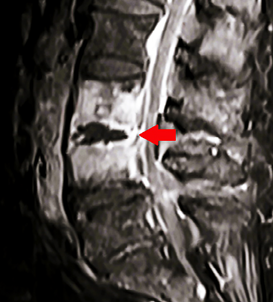

B. MRI (Gold standard

for spinal infection)

·

T1-weighted:

Hypointense vertebral body and disc signal.

T2-weighted/STIR:

Hyperintense vertebral bodies, disc, and paraspinal soft tissues.

Contrast-enhanced:

o

Rim-enhancing epidural abscess.

Enhancement of vertebral bodies and

disc.

Epidural space:

Compression of thecal sac or spinal cord.